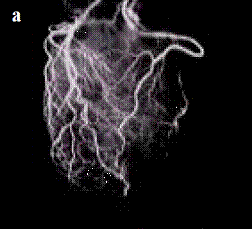

Figura 5. Arterele coronare - piese anatomice injectate cu substanta de contrast si radiografiate: a) in vitro; b) la cadavru